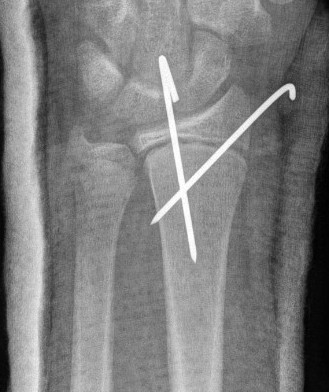

Percutaneous pinning with K wires

Technique

Radial styloid K wire

- small incision, dissect down to protect sensory radial nerve

- avoid physis if able in metaphyseal fracture

- can cross physis

Dorsal Kapaji technique K wire